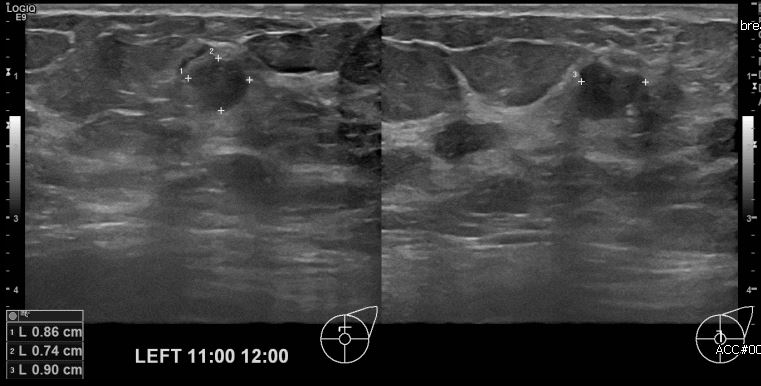

상기환자 양측 유방의 통증으로 내원하신 60대 여성분으로 본원 초음파상 좌측 11시에서 12시 방향에 으심스러운 멍울 조직검사 시행하여 좌측 점액암 진단되었습니다.